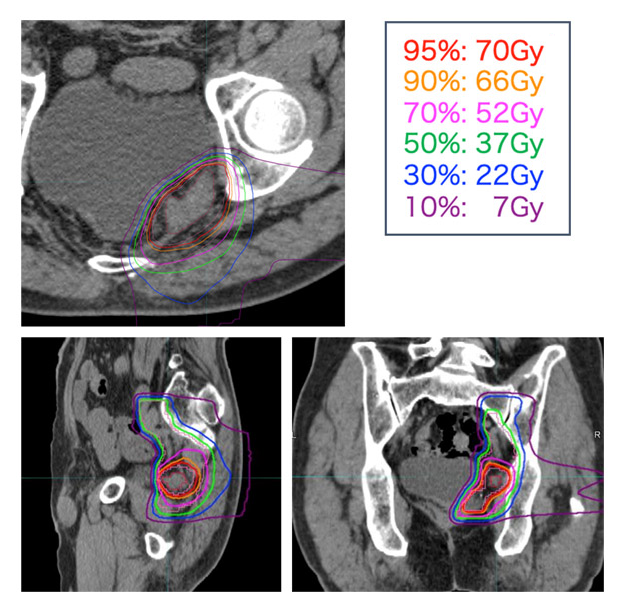

担当医師が患者さんの適格性(治療にあたって問題がないか)を確認します。適格と判断された場合は説明文書に沿って患者さんに治療内容を説明し、文書による患者さんの同意を得ます。その後、所内のキャンサーボードにて審議し、承認を得て初めて治療可能となります。治療準備として、まず固定用の装具を作成します。翌日以降に治療計画用のCT撮影を行い、治療計画を行います。準備には約12日間を要します。重粒子線治療は4週間かけて73.6Gyまたは70.4Gy/16回で行います。重粒子線治療中は化学療法の併用は行いません。重粒子線治療後の後治療は規定していませんが、標準的な抗がん剤を用いた維持目的の化学療法を行っていただくことも可能です。

図 治療計画

実際の治療計画では、周囲の膀胱や消化管などの正常組織への線量を考慮しながら、腫瘍へ十分な線量が照射されるよう配慮します。また、外科的な郭清の概念にならい、再発腫瘍だけでなく周囲のリンパ節領域も可能な限り照射野に含めることで、再燃・再発のリスクを抑えます。

図 照射野